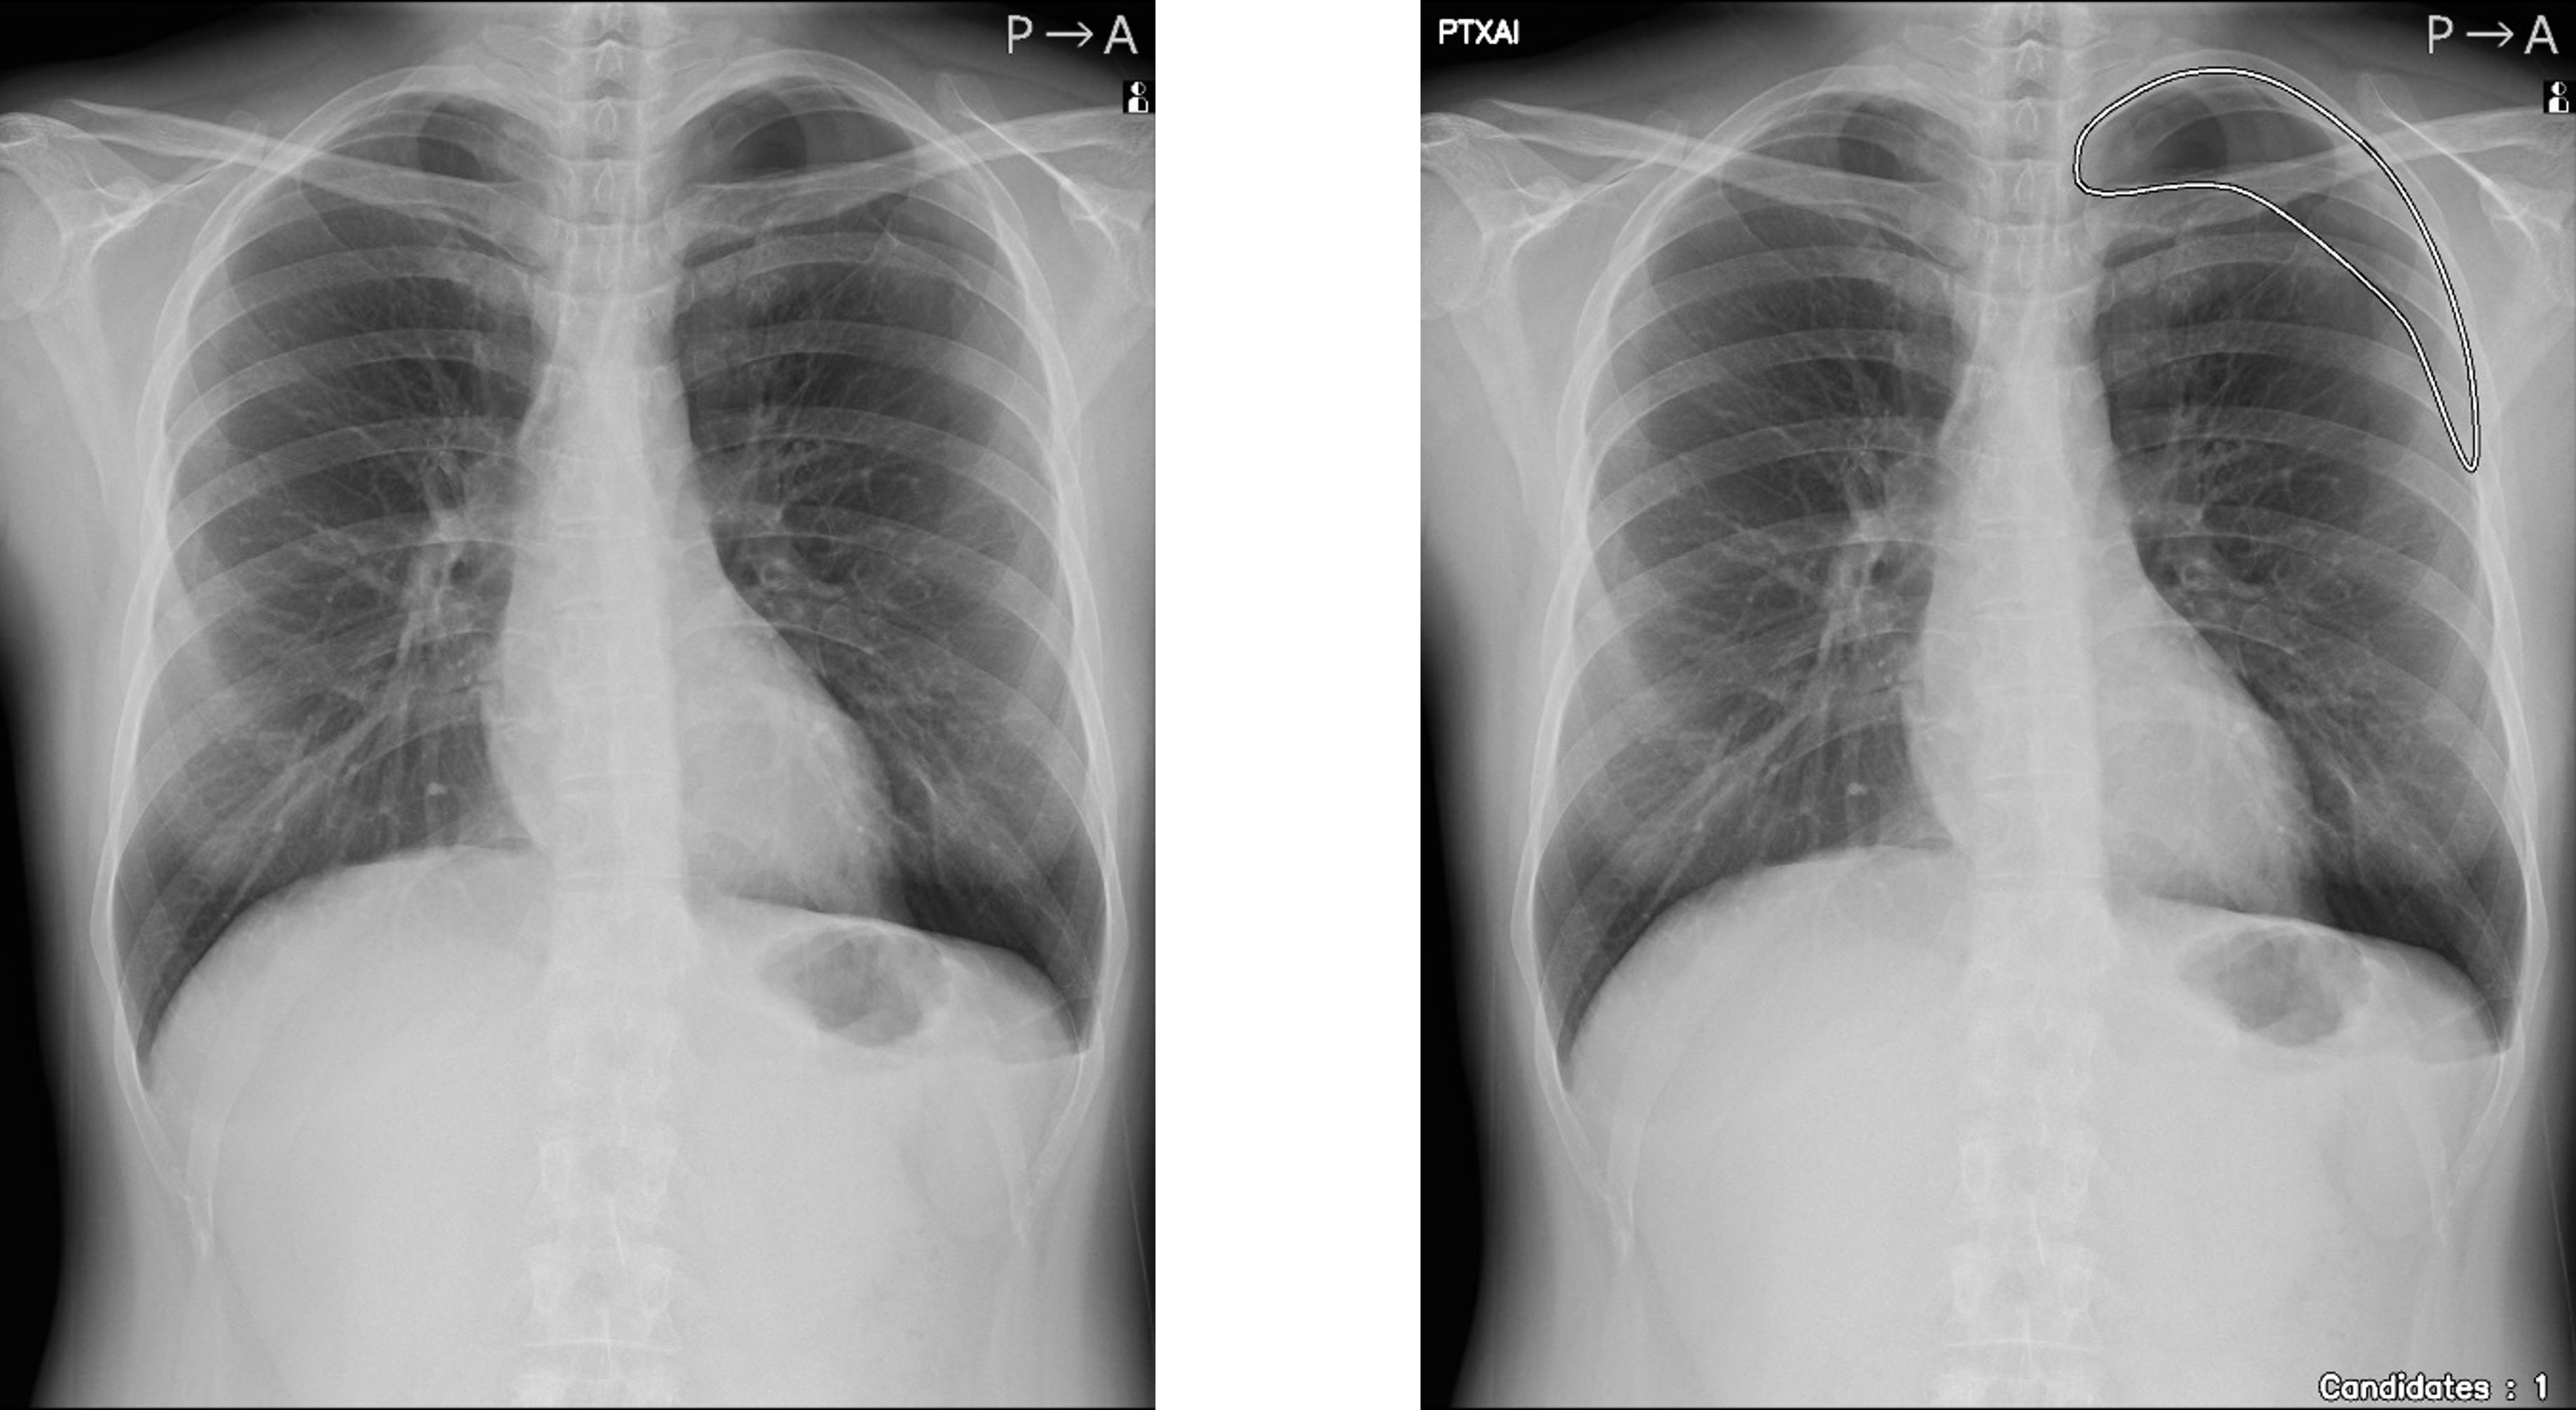

気胸の診断支援を行うプログラム「CXR Finding-i 気胸検出タイプ」と連携することで、ガイドラインにおいて一般撮影で診療放射線技師が発見した場合に報告すべきSTAT画像所見の一つに挙げられている気胸の候補を高精度で検出することができます。

「CXR Finding-i 気胸検出タイプ」により解析された気胸の検出領域を表示

「CXR Finding-i 気胸検出タイプ」は、胸部単純X線画像をAI※2で解析することで重要所見である気胸の候補を迅速に検出し、候補領域を画像上に表示することで見落とし防止を支援します。病変検出性能を示す指標である感度※3は95%と高い水準を実現していることに加え、気胸が存在しない画像をAIが正しく陰性(気胸なし)と判断した割合を示す特異度※4は96%であり、病変を見逃さないようにしつつ偽陽性も抑制した高精度の検出性能が特長です。

人のレントゲン写真 オリジナル画像

オリジナル画像

人のレントゲン写真 気胸の検出領域を表示

気胸の検出領域を表示